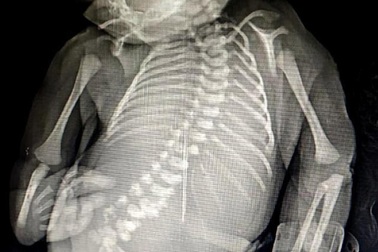

Em bé “người cá” chào đời ở Ấn ĐộEm bé “người cá” thứ hai ở Ấn Độ đã chào đời ngày 6.12, và sống sót được trong 4 giờ.

Em bé người cá xuất hiện tại Ấn ĐộTất cả mọi người đều hết sức ngỡ ngàng khi thấy em được sinh ra với đôi chân dính liền thành một nhưng hai bàn chân lại tách ra như đuôi cá.

15 phút cuộc đời ngắn ngủi của em bé “người cá” sinh ra tại Ấn ĐộMột bà mẹ ở miền Tây Ấn Độ đã sinh ra con “người cá” và đau đớn nói lời từ biệt đứa trẻ 15 phút sau khi sinh.